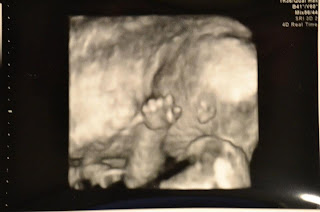

It's a...

....girl!

Jason and I are really excited to be parents, and we cannot wait to just meet our sweet baby girl.  I can't believe she's already so big!  I don't really look all that pregnant, just kind of bloated, so it was a surprise to see a baby looking back at us that already has a profile.